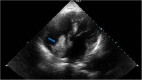

Case presentation: We are reporting a case of recurrent HCC with an accidentally discovered direct right atrial extension with tumor thrombus through the inferior vena cava (IVC) in a cirrhotic patient previously treated with DAA. Unfortunately, due to his critical general condition, he died within days.